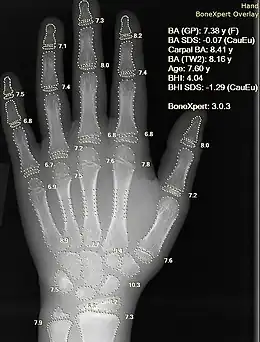

Rayon X d'une main, avec calcul automatique de l'âge osseux par un logiciel informatique.